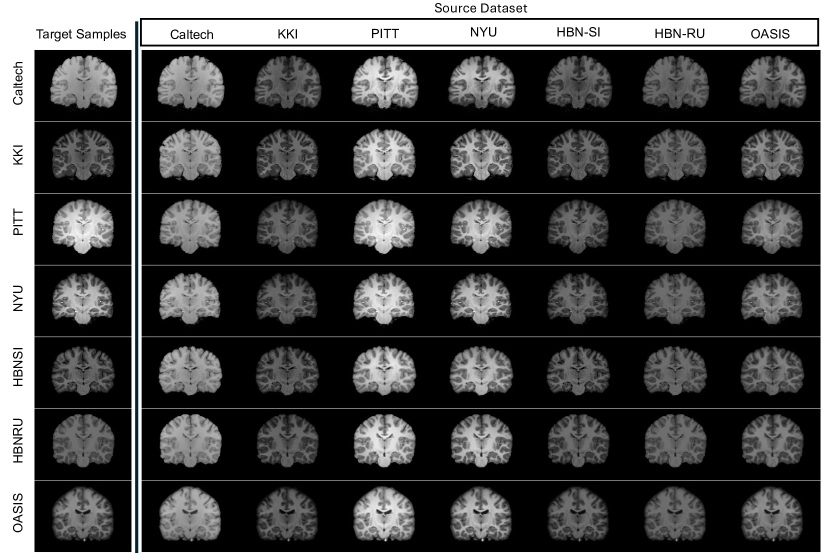

Figure 7: This figure showcases examples of harmonized images generated by the proposed method. The first column presents the sample images from various target domains. The subsequent columns display the images harmonized to specific source domains, as indicated at the top of each column. Therefore, each row maintains consistent anatomical structures, while each column shares the same visual characteristics.

Fig. 7 showcases the instances of harmonized images using the proposed method across different source and target sites, for the adult brain MRIs. In particular, we randomly picked a sample from each site and then mapped it to different target sites. As can be seen, the harmonized samples in each column share the same visual characteristics, while on each row, the details of the harmonized images are preserved. These qualitative results illustrate that, regardless of the source or the target domains, the proposed method consistently produces reliable harmonized images, which is supported quantitatively by the comprehensive empirical validation conducted. Furthermore, visual examples depicted in Fig. 8 (neonatal brains) demonstrate the effectiveness of our approach in harmonizing inter-site images, regardless of the modality and plane used.